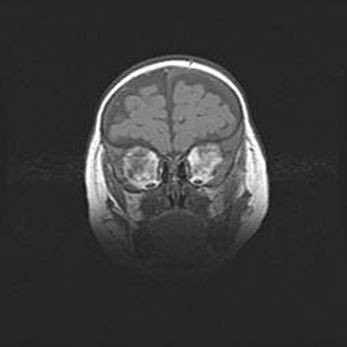

Наружная гидроцефалия с возможной атрофией височных областей.

Возраст: 28 дней

Вес: 3670 г

Пол: мужской

Окружность головы: 38 см

Срок гестации: 40 недель

Гидроцефалия головного мозга у новорожденных – это заболевание, которое характеризуется скоплением избыточного количества спинномозговой жидкости в желудочковой системе головного мозга в результате затруднения её перемещения от места выработки к месту поглощения в кровеносную систему или вследствие нарушения абсорбции. При открытой наружной форме гидроцефалии у новорожденных расширяются и переполняются субарахноидные пространства.

При нормотензивных  формах,  которые,  как  правило,  являются  следствием  перенесенных ишемических  повреждений  паренхимы  мозга,  возможно  сочетание микроцефалии  с нормотензивной гидроцефалией. В основе данных изменений лежит атрофия больших полушарий с преимущественной  локализацией  в  лобно-височных  областях.